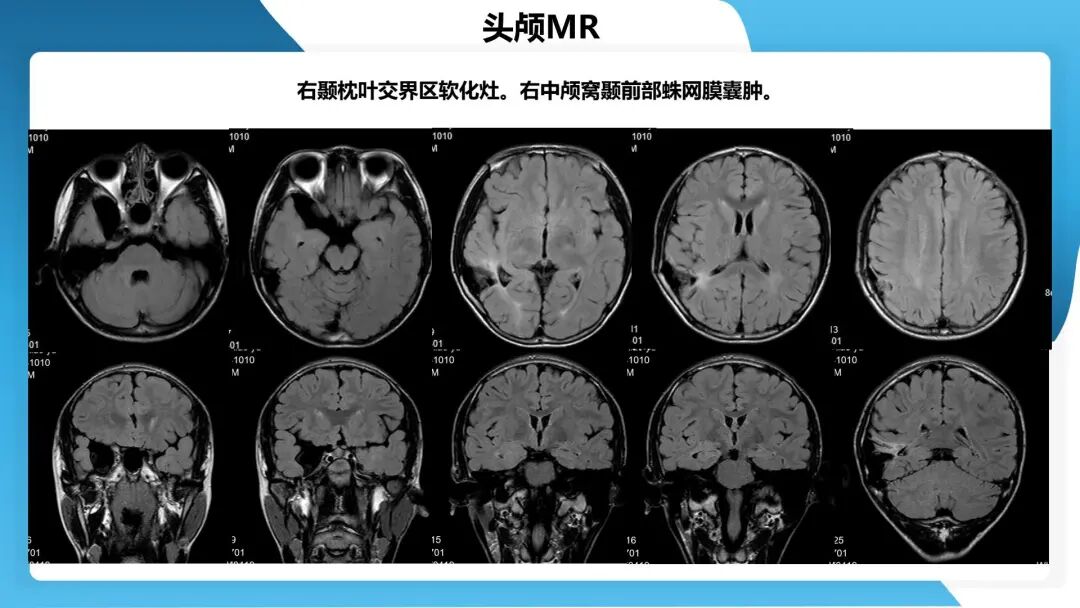

《「痫停」信步》癫痫治疗病例荟萃第四十四期---颞前叶及脑软化灶切除治疗难治性癫痫一例